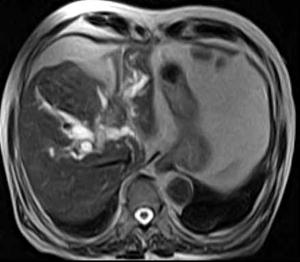

А

Рисунок 10 – А – КТ-изображение холангиокарциномы;